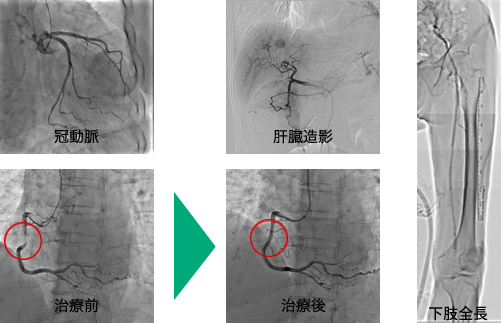

血管造影検査

カテーテルという細い管を腕や太ももの付け根の血管から目的血管まで挿入し、造影剤を使用して撮影し必要に応じて治療まで行います。血管が狭くなったり、詰まったりしていないかなど血管自体、また血管が関与している疾患を詳しく調べ、必要があればIVRと呼ばれる血管撮影手技を応用した治療、例えば心臓の冠動脈に対するバルーン治療やステント挿入術・肝臓癌の血管塞栓術や動注療法などを行っています。

当院の血管造影撮影装置は、FPD(フラット・パネル・ディテクター)と呼ばれる検出器を搭載している為、従来より診断能力の高い鮮明な画像を提供する事が可能になりました。また、従来の装置は心血管のみが対象でしたが、腹部血管、下肢血管も造影の対象になりました。詳しい内容は医師へお気軽にお尋ね下さい。